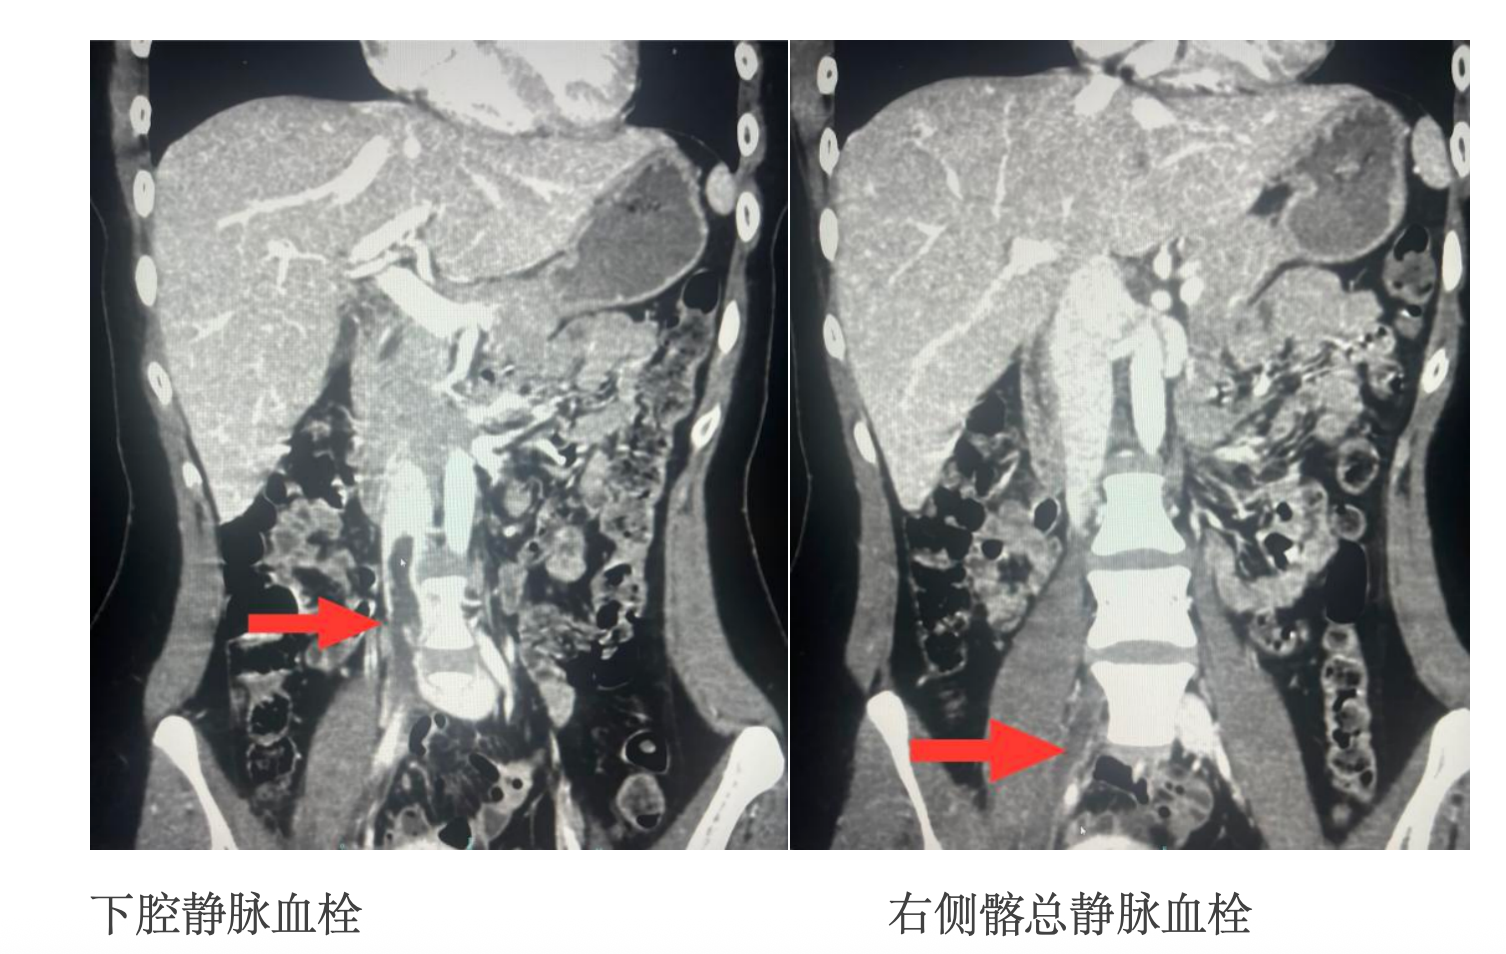

检查结果令人震惊:彩超与CT显示,小玲从肾静脉水平以下的下腔静脉,到右侧整条髂总静脉、股静脉、腘静脉,乃至肌间静脉,几乎全程被血栓堵塞!更危险的是,部分血栓已脱落造成急性肺栓塞。

此时的小玲汇配资,右腿高度肿胀,血管内的血栓如同“不定时炸弹”,随时可能因轻微活动引发更大范围肺栓塞,导致猝死。